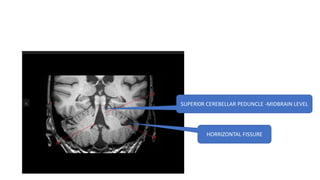

SUPERI0R CEREBELLAR PEDUNCLE -MIDBRAIN LEVEL

HORRIZONTAL FISSURE

SUPERIOR CEREBELLAR PEDUNCLE -MIDBRAIN LEVEL

MIDDLE CEREBELLAR PEDUNCLE AT PONS